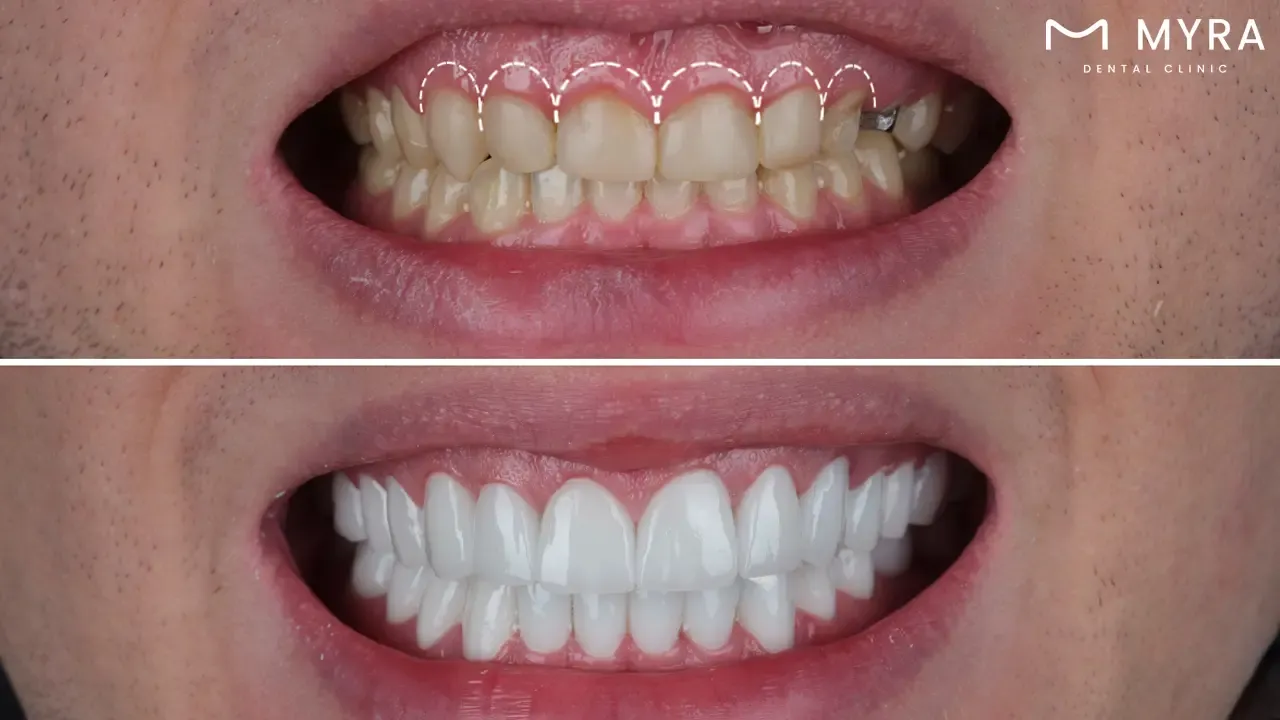

3. Veneers in Turkey

Veneers are thin, customised shells made of porcelain or composite resin. The shells are intended to be bonded to the front surface of teeth which improves their appearance by concealing defects and increasing overall attractiveness. Veneers are used to treat dental concerns such as discolouration, staining, chipping, misalignment, and gaps between teeth. Individuals get a brighter, more symmetrical, and natural-looking smile by glueing the shells to their teeth.

The cost of veneers varies considerably due to several influencing factors. A single veneer ranges from £500 to £1,100 in UK. The actual cost depends on several variables, including the choice of veneer material, the number of veneers required for treatment, the complexity of the dental case, the geographical location of the dental practice, and the reputation of the dentist. The cost is higher for a complete set of dental veneers.However, dental veneers in Turkey are more affordable and of high quality, making it a great option for those seeking budget-friendly and reliable cosmetic dental treatments.

Veneers have several benefits, the majority of which revolve around aesthetic enhancements. They are quite effective at improving the appearance of teeth by addressing concerns such as discolouration, staining, chipping, misalignment, and gaps. Veneers, particularly those made of porcelain, closely resemble the natural appearance of teeth in terms of colour, translucency, and texture, producing an incredibly lifelike outcome. The technique is comparatively minimally invasive and slightly reduces the amount of tooth enamel compared to certain other dental restorations. Veneers provide speedy results, delivering an immediate transformation for people looking for quick smile makeovers. In Turkey, porcelain veneers are highly stain-resistant, allowing people to maintain a dazzling smile for an extended period of time.

Veneers come with certain considerations, despite the many advantages they provide. Cost is an important consideration because veneers are pricey, especially when several veneers are needed or when people choose porcelain veneers. However, veneers in Turkey are more affordable compared to other countries, providing high-quality treatment at a lower cost. The removal of a tiny layer of enamel from the teeth during the veneer preparation process makes the operation irreversible. Maintaining veneers is not indestructible and is susceptible to harm by behaviours such as teeth grinding or biting hard things. Veneers have a limited lifespan and need to be replaced after a few years due to causes such as wear and tear. Remember that veneers are a cosmetic solution and are not appropriate for treating dental conditions that need more thorough treatment.

Veneers are normally treated over a series of sessions. Veneers start with initial consultations, dental impressions, and tooth preparation, which need one or two sessions. Unique veneer creation by a dental laboratory takes several weeks. Veneer installation and bonding are completed in a single appointment per arch. The entire procedure takes between two and four weeks from the initial consultation to the finished product, allowing people to enjoy a new smile in a short amount of time. In Turkey, this efficient process is available at highly competitive prices, making it an attractive option for dental tourism.